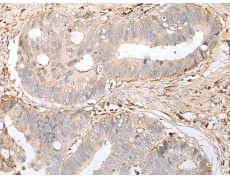

ELISA, IHC |

IHC positive control: |

Human cervical cancer and human gastric cancer |

IHC Recommend dilution: |

25-100 |